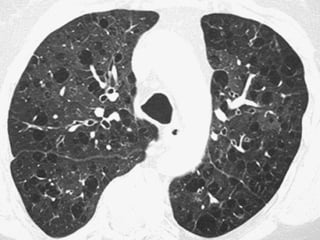

 TCAR  Extensãodo acometimento pulmonar e fase da dça. ▪ Precoce: áreas em vidro fosco ▪ Avançada: faveolamento FIBROSE PULMONAR IDIOPÁTICAFIBROSE PULMONAR IDIOPÁTICA

 Padrão definitivo– Todos os 4 critérios são necessários:  Predominância nas bases e regiões subpleurais;  Anormalidades reticulares;  Faveolamento com ou sem bronquiectasias de tração;  Ausência de todos os 7 critérios inconsistentes com o padrão de UIP FIBROSE PULMONAR IDIOPÁTICAFIBROSE PULMONAR IDIOPÁTICA

FIBROSE PULMONAR IDIOPÁTICAFIBROSEPULMONAR IDIOPÁTICA Fonte: http://www.scielo.br/scielo